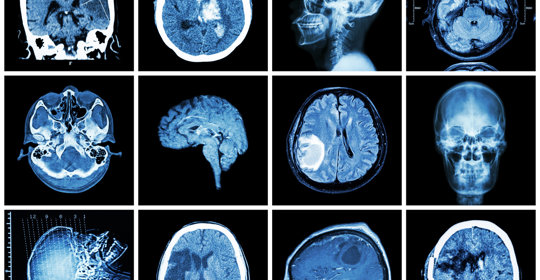

大腦與神經

顱神經麻痺:治療與管理策略

顱腦損傷後頭痛:原因、治療與就醫建議

顱神經麻痺:症狀、原因及後遺症

顱神經損害:不同型別的症狀與診斷

顱神經麻痺:自律神經失調

顱神經麻痺:症狀、原因及治療方法

顱腦損傷後頭痛:原因與處理方法